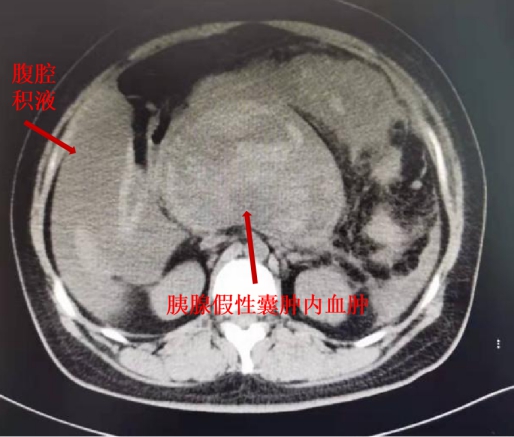

急检显示患者血红蛋白只有50g/L,还不到正常值一半,腹部高度膨隆、CT显示腹腔大量积液,诊断性腹腔穿刺抽出新鲜血性液体,接诊后,重症医学科杨松林教授立即为患者进行抗休克、扩容、脏器功能保护等生命支持治疗,并第一时间请胰腺专科团队会诊。

术中,陈华教授、王拥卫副教授以最快的速度入腹清除胰腺假性囊肿腔内的血凝块及坏死组织,找到出血点进行确切止血,随后对胰腺假性囊肿进行充分外引流,术中清除血凝块及血性积液共计约3500ml。入院仅数小时后,患者手术成功、转危为安。术后,患者病情迅速好转,转入普通病房,并已于近日康复出院。